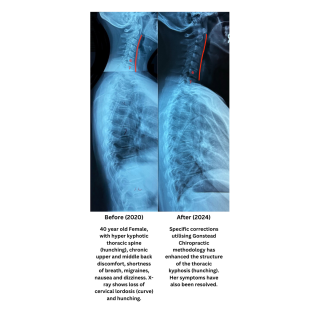

Hyper kyphosis (Hunching) of Thoracic Spine Causing A Reversal Of Cervical Spinal Curve